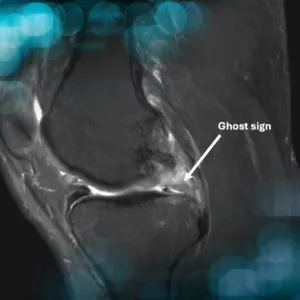

Tears of the posterior meniscal root significantly compromise the ability of the meniscus to convert axial loads into circumferential hoop stresses, resulting in loss of meniscal function and increased joint contact pressures

Accurate and timely diagnosis of lateral meniscus radial tears is crucial. These tears disrupt circumferential fibers, impairing meniscal function and joint stability. Often underdiagnosed on imaging, they require careful arthroscopic evaluation when suspected.